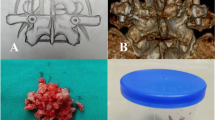

MI-TLIF involved making an incision of 2.5 cm length 2.5 cm off from the midline and dividing the muscles in order to separate multifidus and longissimus and to approach the laminar and the facet joint. Once lumbar facet joints are visualized, we set a delicate spinal traction and removed the inferior and the upper half of the superior articular processes along with yellow ligaments using a surgical microscope to visualize the nerve roots and the dura mater passing over the superior pedicle. And we performed lumbar discectomy. We then distracted the lumbar intervertebral distance gradually using a shaver and denuded the superior and inferior end plates in preparation for the fusion. We filled a spine cage (Capstone; Medtronic, Memphis, TN, USA) with a local autobone. It was obtained from articular process and lamina during decompression. We removed cartilage and soft tissue from obtained local autobone through rongeur and cut obtained local autobone about 3 mm sized.

A single cage was used for each patient. For Group I, a local bone was additionally harvested from the iliac crest for autograft. In case of Group II and III, the leftover autobone from cage filling was mixed with HA and used to fill the intervertebral space to allow bone fusion outside the cage (Fig. 1). After inserting the cage, we fixed the posterior cage with screws.